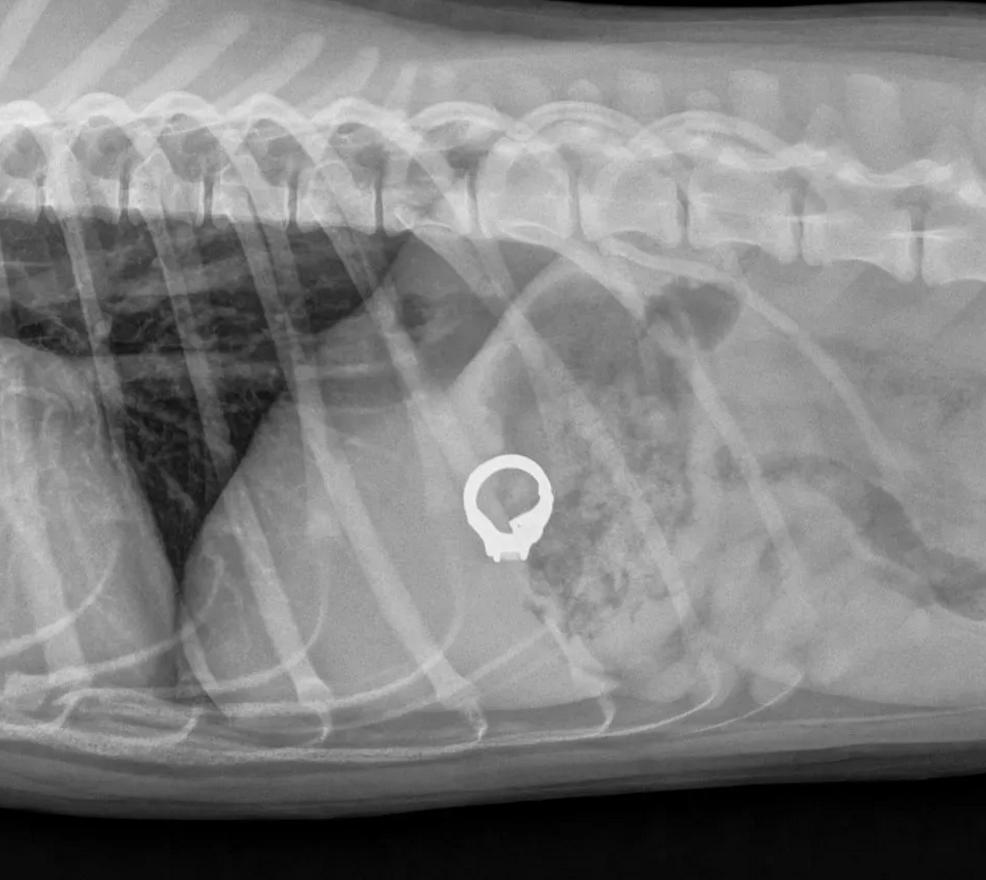

比如上面这只巨型犬贵宾犬就更厉害了,它居然把铲屎官的戒子吃了下去,不过这家伙运气很好,因为刚吃下去就被主人发现了。

主人洗澡时,把戒指放桌子上,结果被狗狗吃下去。

泰国网友家的巨型贵宾犬一样是个吃货,它趁铲屎官进浴室时,把主人平时带的戒子给吞了下去,还好铲屎官及时发现,马上带毛孩子去了医院。